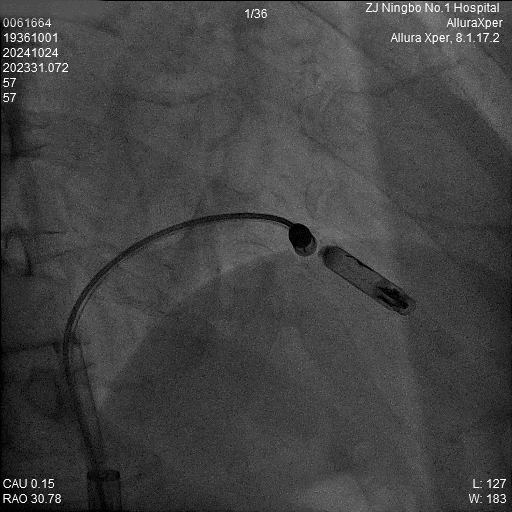

1.猪尾导管造影:软钢丝配合猪尾导管进入RV,造影显示RV轮廓。

a)RAO 30